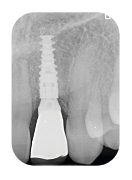

Module II – Les empreintes

- Les empreintes physiques (ciel ouvert et ciel fermé) : indications et spécificités

TRAVAUX PRATIQUES - Les empreintes optiques : l’environnement numérique de la prothèse

sur implant de A à Z - DÉMONSTRATION CLINIQUE EN DIRECTE suivie de TRAVAUX PRATIQUES